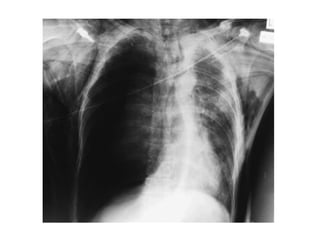

• The chest radiography findings are typically

delayed and non-segmental.

• Contrast CT scanning can be confirmatory.

• If abnormalities are seen on the admission chest

radiograph, the pulmonary contusion is severe.

• The naturalprogression of pulmonary contusion is worsening hypoxemia for the first 24–48 hours. • The chest radiography findings are typically delayed and non-segmental. • Contrast CT scanning can be confirmatory. • If abnormalities are seen on the admission chest radiograph, the pulmonary contusion is severe. • Haemoptysis or blood in the endotracheal tube is a sign of pulmonarycontusion